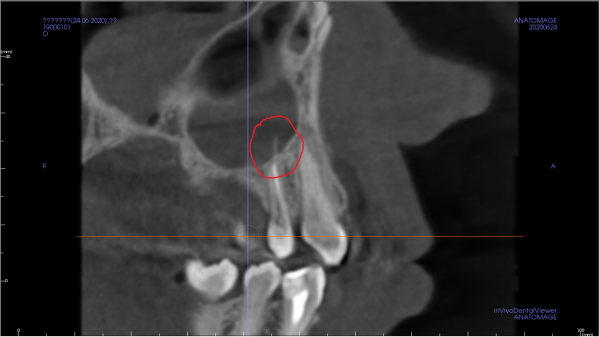

На КТ снимке просматривается затемнение левой верхнечелюстной пазухи, а также небольшой узкий тяж, идущий от четверки. Ранее проводилась операция по удалению кисты и резекции верхушки корня на двойке.

Может ли так просматриваться корень зуба и корень ли это? Насколько опасно наличие этого тяжа в пазухе?